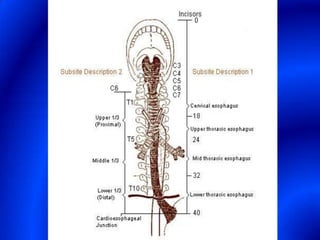

This document provides information about a barium swallow procedure. It begins with an introduction and overview of the embryology and anatomy of the pharynx and esophagus. It then describes the procedure itself, including preparation, technique, views obtained, and indications. Specific conditions that may be examined include pharyngeal and esophageal webs, foreign body impaction, scleroderma, dysphagia, mediastinal masses, and carcinoma. Diagrams are provided to illustrate normal anatomy and various pathological findings.